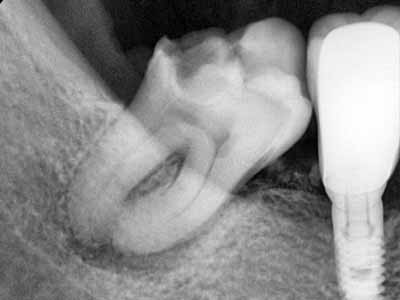

Frontier in Micro Dentistry and Endodontics

drg. Dennis,MDSc.,Sp.KG, Subsp. KE(K)., Ph.D

Dokter Gigi Spesialis Konservasi Gigi Konsultan, Master of Dental Science